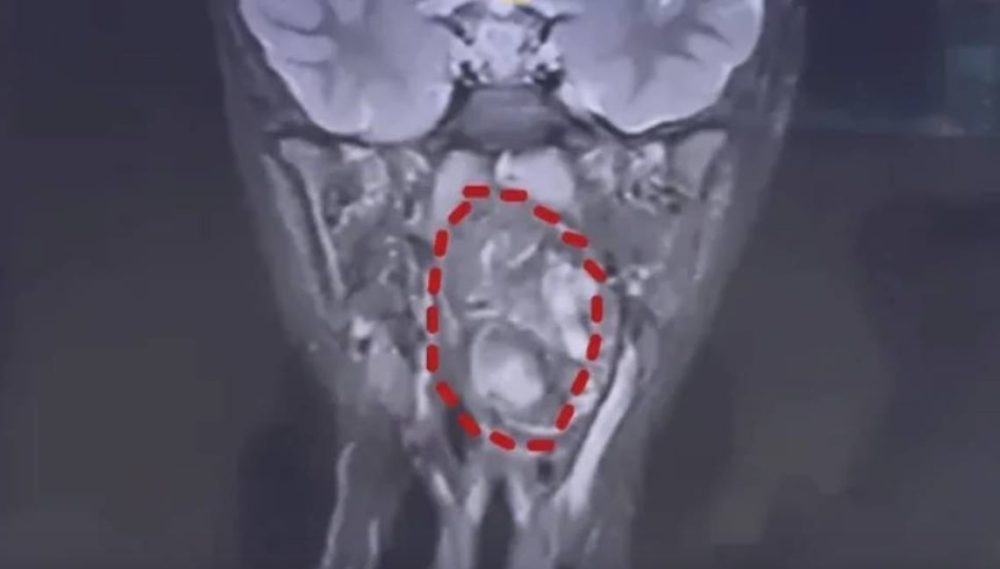

男童小亮为化名。医生检查发现,他的口咽腔约8公分,但肿瘤已长至6.6公分,占据大部分气道,孩子只能靠剩下的狭窄缝隙呼吸。若未及时处理,随时可能出现窒息风险。

负责诊治的耳鼻咽喉头颈外科副主任陈超医生表示,该肿瘤是由生殖细胞演变而成的畸胎瘤。医生在肿瘤内可见脂肪、软骨等组织,因此推断这可能原本是一对双胞胎,其中一个正常发育成小亮,另一个则残留并形成畸胎瘤。

医生指出,畸胎瘤多数属良性,较常见于腹腔;出现在儿童咽喉部位,且体积如此巨大,则相当罕见。更棘手的是,肿瘤紧贴颈部大动脉,增加手术难度及风险。